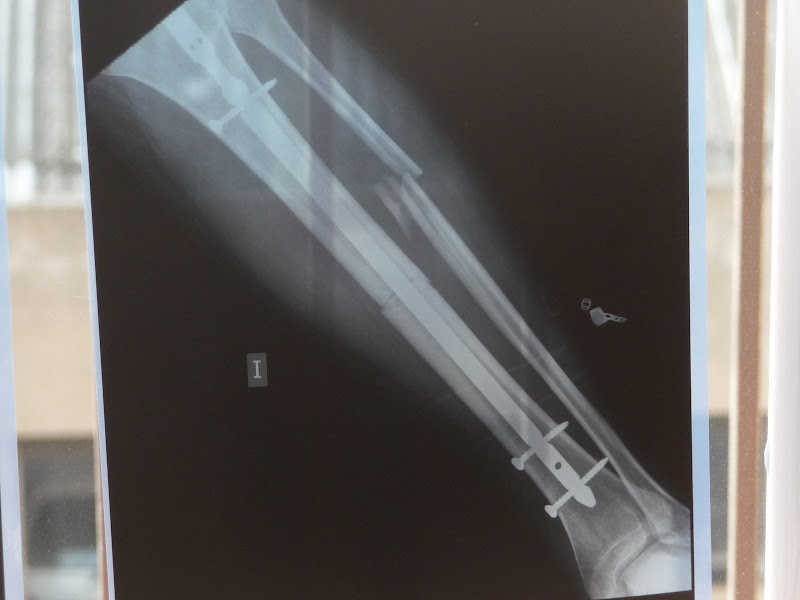

Doncs de moment bé. Jo vaig movent cada cop mes la cama, i l'Esther cada dia mes cansada de cuidar-me, jeje. Avui hem anar a veure el metge, m'han fet unes radiografies (que he aprofitat per fer unes fotos) i diu que tot va molt be, que si segueix aixi, a finals d'abril podre posar el peu a terra.

Sergi3 ha escrit:........ m'han fet unes radiografies (que he aprofitat per fer unes fotos) ............

NO FOTOS= NO RADIOGRAFIA :mestre

Randy-650 ha escrit:

Ale, si foto=si radiografia :D

Aixo ho arreglen com qui posa 4 cargols per arreglar un armari

Imatge

Ostres que xules, jo vull un ferro així !!!!

Auughh!! M'ha fet mal a mi i tot de veure-les.

Deu ni dò. I aquest peronè? tot sol ja es posarà a lloc?

A mi també en fa mal només de veure-ho. :shock:

Sort que en sergi és un HOME de veritat, no com molts de nosaltres que només ho semblem. :!:

Amb aquesta trencada i no va dir practicament ni piu, és un HOME de dalt a baix. :wink:

Vendetta ha escrit:Deu ni dò. I aquest peronè? tot sol ja es posarà a lloc?

Aixó diu el metge, i que si no no passa res, pero jo no les tinc totes. Ell ni li va donar gaire importancia.